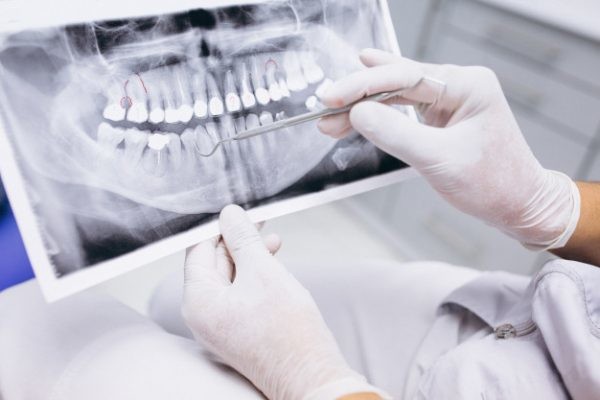

A dental professional or specialist (usually an endodontist) may diagnose a fracture during a root canal procedure if they can see a crack. If the fracture occurs after the procedure, they might need to take X-rays, which may show the fractured root characteristically shaped like the letter J, or the specialist may also use a diagnostic method known as transillumination, where they shine a light through your tooth to detect any fracture lines.

Small dentigerous cysts often go unnoticed until you have a dental X-ray. If your dentist notices an unusual spot on your dental X-ray, they may use a CT scan or MRI scan to make sure it’s not another type of cyst, such as a periapical cyst or an aneurysmal bone cyst.